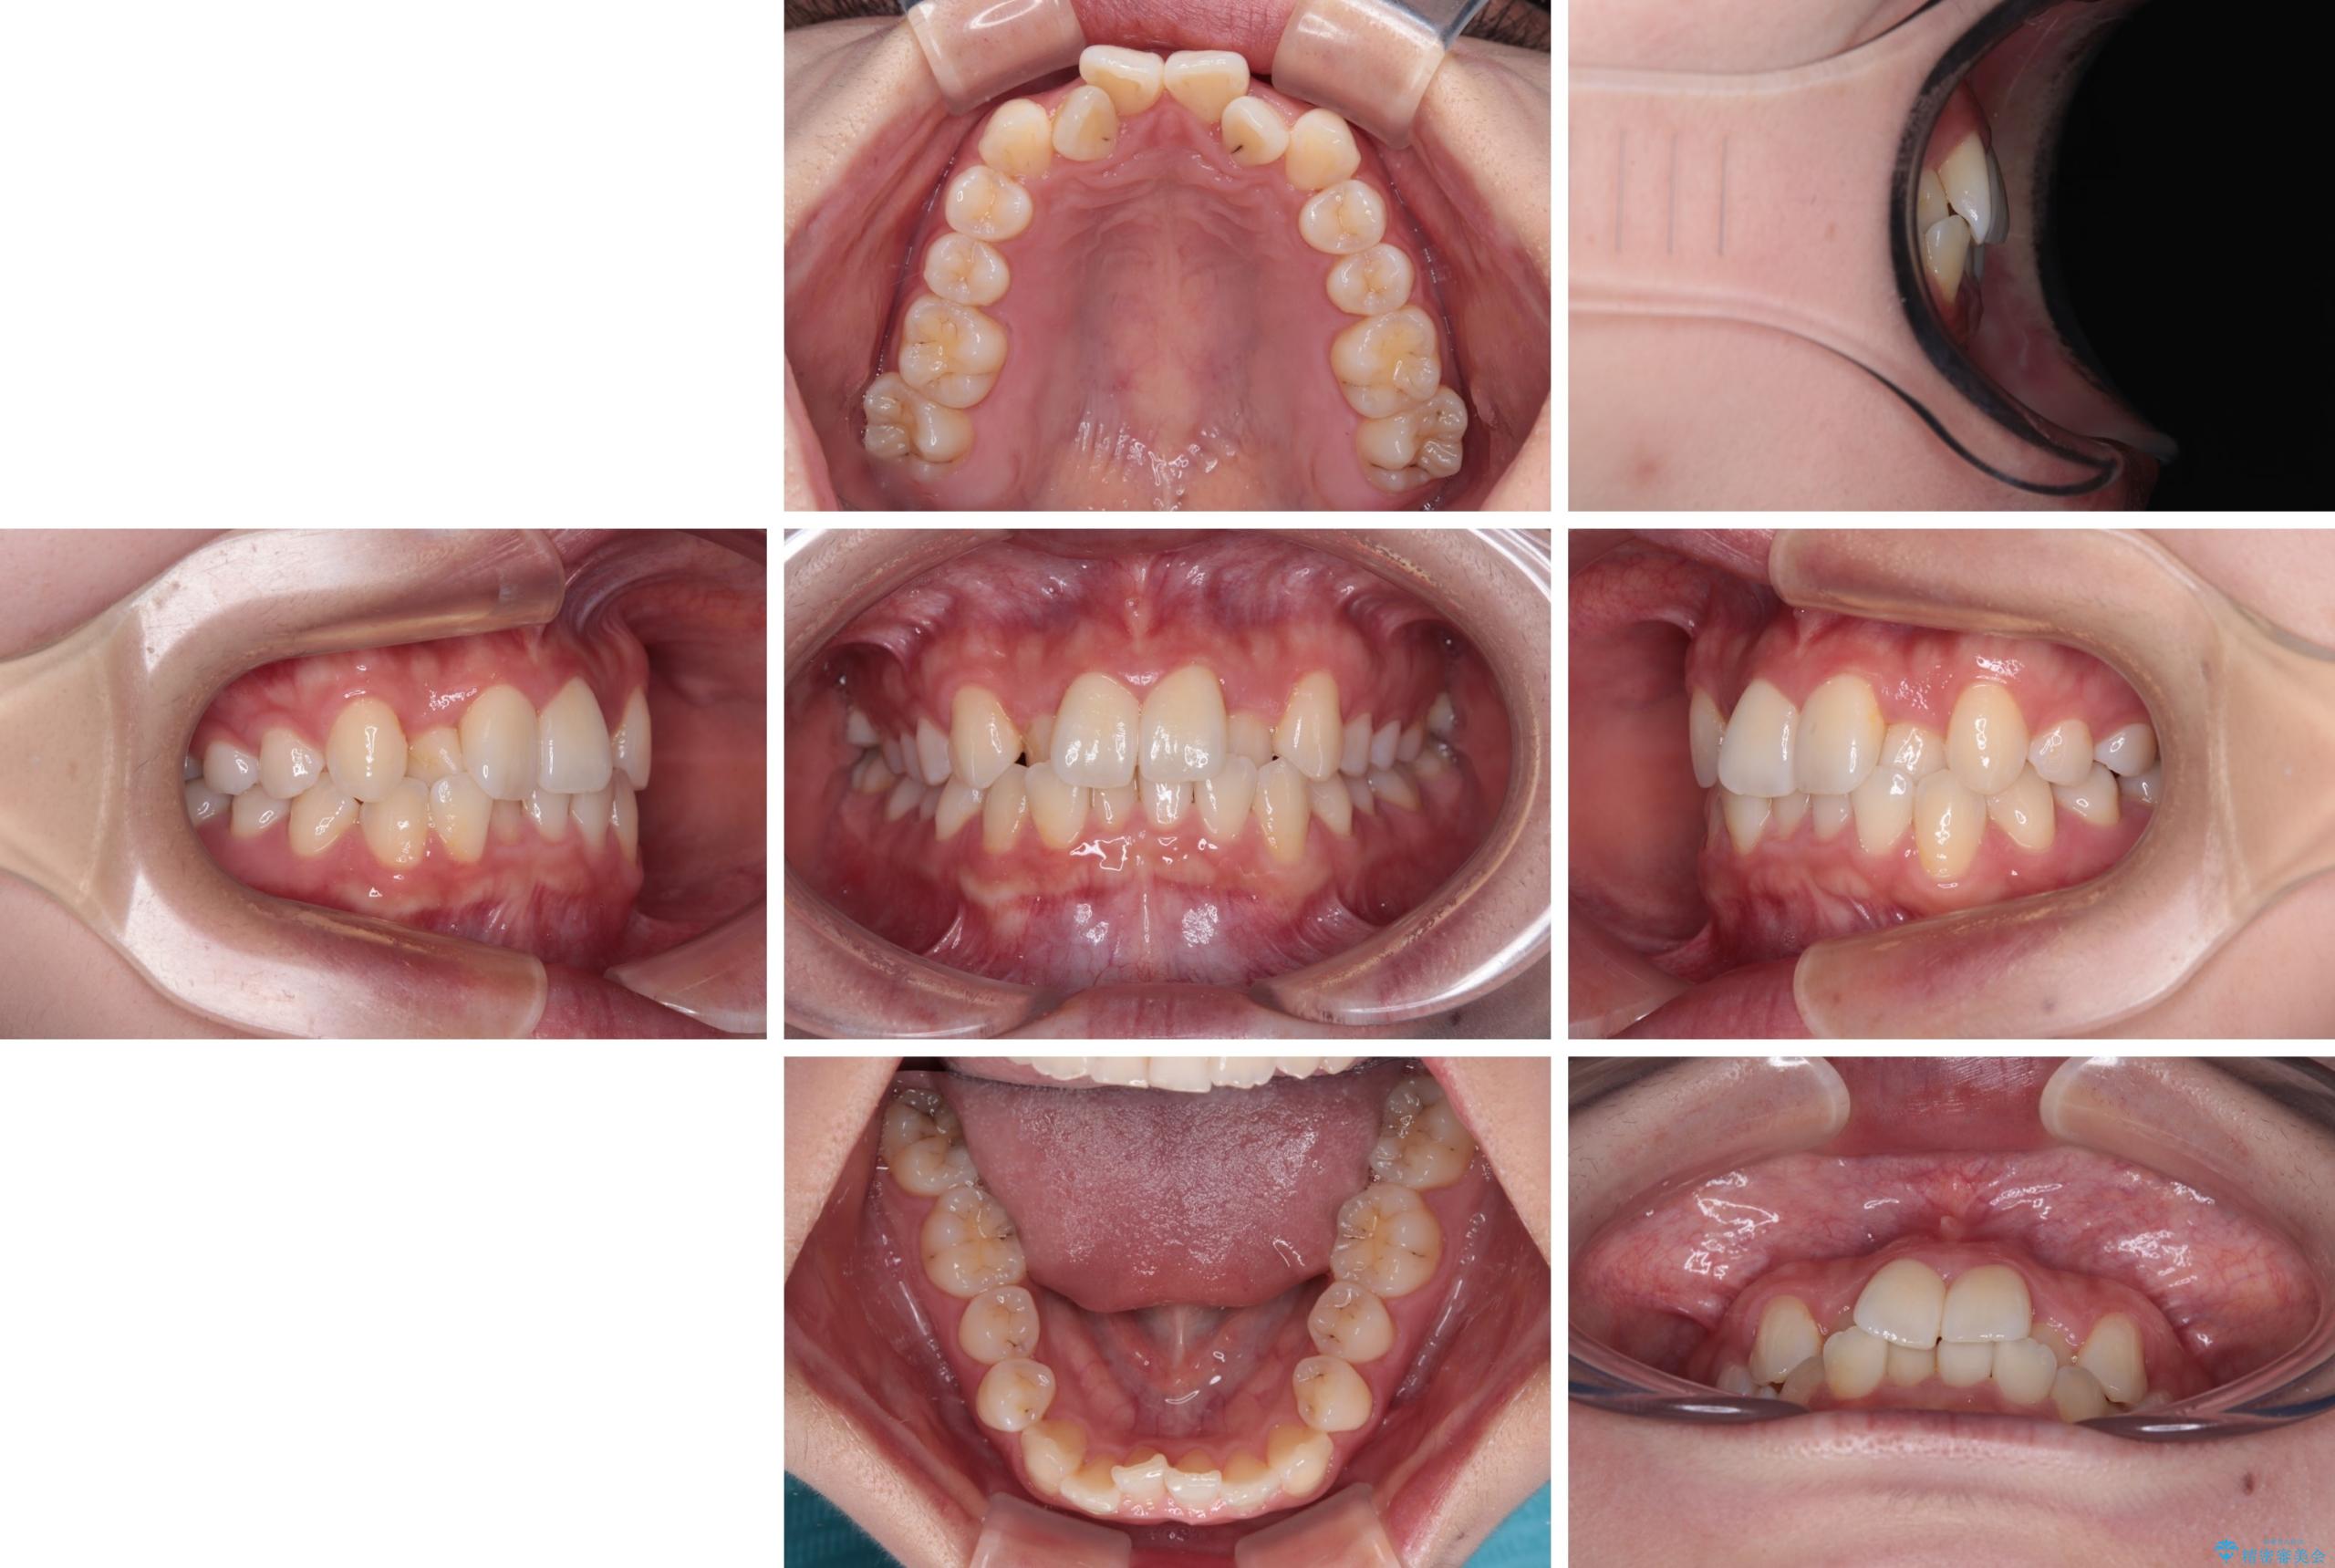

- 上顎前歯のクロスバイトを気にして来院された患者様です。

ワイヤー矯正でもマウスピース矯正でも対応可能でしたが、マウスピースによる自己管理に一切の自信がないとのことで、ワイヤー装置にて矯正治療を行うこととしました。

装置の外見を気にしていましたが、短期間で治療を終えることができるだろうと伝えると、安価であるメタルブラケットを選択されました。

想定通り、1年強で綺麗に仕上げることができました。